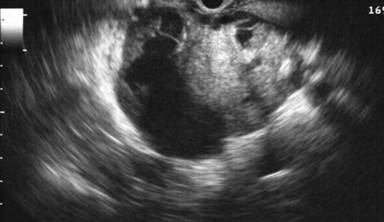

Figure 3. EUS findings in a middle age female patient with a mucinous cystic neoplasm in the body of the pancreas. A thick wall and a solid mass are features suggestive of malignancy. Surgical resection confirmed mucinous cystadenocarcinomas. |